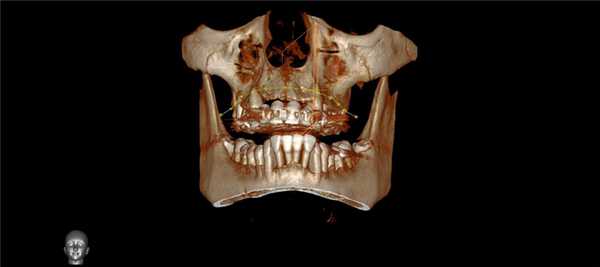

На томограммах и реконструктивных снимках было установлено, что 4.6, 4.7 зубы имеют особенность микроанатомии каналов. Мезиальные корни содержали по 2 канала, которые открывались отдельными апикальными отверстиями. В дистальных корнях обнаружили по 3 канала, которые сливались в одно апикальное отверстие. Причем третий (дистально-язычный) канал 4.7 зуба заканчивался на язычной стенке корня на уровне его середины (рис. 2) .

Рис. 2. КЛКТ. Аксиальные последовательные срезы 4.6, 4.7 зубов.